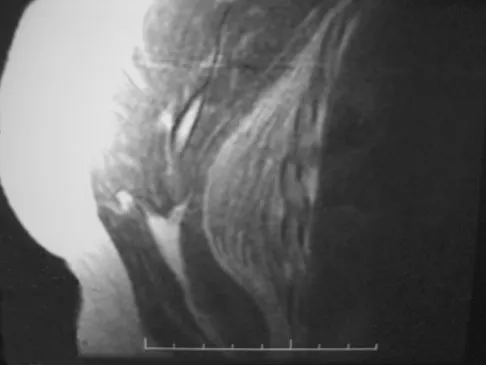

A 36-year-old woman has pain and swelling of the anterior arm after undergoing arthroscopic shoulder surgery 8 months ago. At the time of the procedure, extensive debridement and synovectomy of the anterior aspect of the joint was performed to remove scar tissue that had formed after an open rotator cuff repair. Examination reveals a golf ball-sized swelling just lateral to the coracoid. The area is not warm and shows no other signs of infection. An MRI scan is shown in Figure 1. Management should now consist of

A 28-year-old woman who is training for the New York Marathon reports pain in the posteromedial aspect of her right ankle. Examination reveals tenderness just posterior to the medial malleolus. Radiographs are normal. An MRI scan is shown in Figure 3. What is the most likely diagnosis?

A 35-year-old woman states that she stepped on a piece of glass 6 months ago and reports numbness and shooting pain along the plantar lateral forefoot. She had previously received steroid injections in the 3 to 4 webspace. Examination reveals mild tenderness along the plantar fascia; no Tinel's sign is noted plantar medially and no Mulder's click is noted distally. An MRI scan is shown in Figure 7. What is the most likely cause of the numbness?

Figure 7 shows the MRI scan of a 23-year-old competitive rugby player who has anterior ankle pain and swelling. He states that he has been playing for many years and has sprained his ankle several times. Examination will reveal what specific hallmark feature?